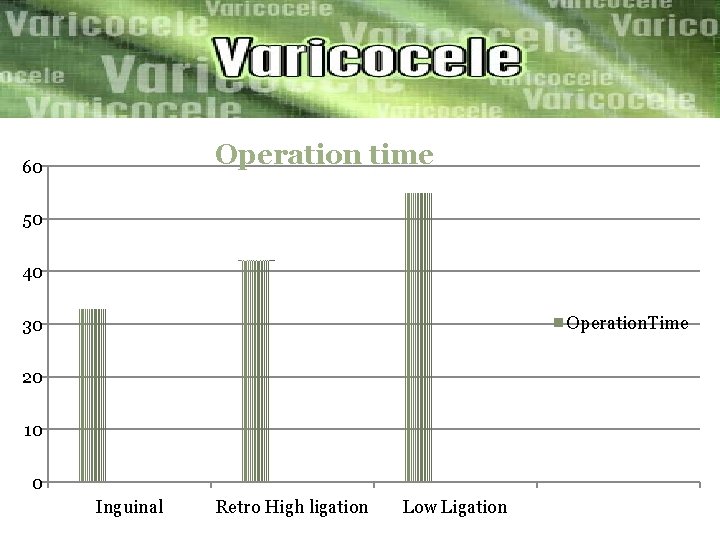

ØWe compare the outcomes of three microsurgical techniques: inguinal high ligation (IHL) =40 patient Retroperitoneal high ligation(RHL) =40 patient Low ligation(LL) =40 Patient we compared the operation time, post operative complication Recurrence rate. The result was…………….

Operation time 60 50 40 Operation. Time 30 20 10 0 Inguinal Retro High ligation Low Ligation